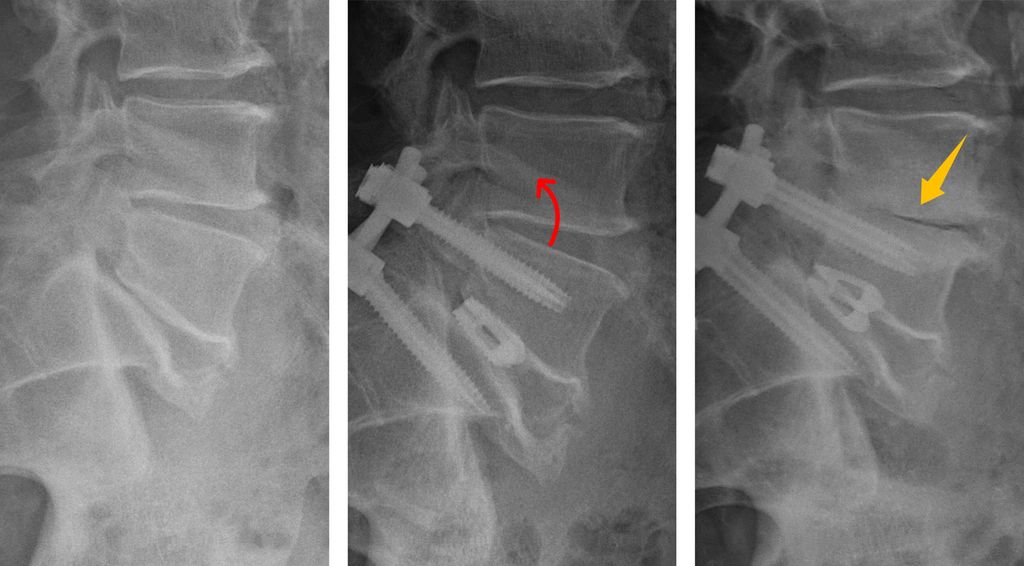

In den vergangenen Jahren hat sich das Verständnis der sagittalen Wirbelsäulenparameter deutlich erweitert und dieses Wissen findet zunehmend Anwendung im klinischen Alltag. Neben klassischen Messgrößen wie der Lendenlordose oder der Beckenneigung werden zunehmend auch individuelle patientenspezifische Zielwerte herangezogen. Aber nicht nur die globale Balance der Wirbelsäule ist hier von großer Bedeutung. Auch bereits eine Deformität eines einzelnen Segmentes kann maßgeblich sein. Eine fehlende oder unzureichende Lordose im operierten Indexsegment zwingt angrenzende Segmente in pathologische Kompensationsmechanismen, um das sagittale Gleichgewicht zu erhalten. Die hierbei auftretende Hyperlordose und Retrolisthese im Nachbarsegment führt zu unphysiologischen biomechanischen Belastungen der Bandscheibe und Facettengelenke (Abb. 1). Dies kann ein Mechanismus und Treiber der „Anschlussdegeneration“ sein. Eigene Untersuchungen zeigten, dass eine konsequente Wiederherstellung der Lordose nach einer monosegmentalen Fusionsoperation das Potenzial hat, die Kompensationsmechanismen im direkt angrenzenden Segment deutlich zu reduzieren (Abb.2 ). Auf solche Erkenntnisse sind zunehmend auch Implantathersteller eingegangen und bieten neue Implantate an, die helfen sollen, die Lordose wiederherzustellen. So finden sich etwa zunehmend hyperlordotische Cages für ventrale wie auch dorsale interkorporelle Verfahren am Markt und eröffnen zusätzliche Möglichkeiten, die sagittale Balance individuell anzupassen.

Abb. 1: Schematische Darstellung von Kompensationsmechanismen (a) mit unphysiologischen Belastungen (b) im kranialen Nachbarsegment bei segmentaler hypolordotischer Deformität L5/S1 sowie Reduktion derselben bei Wiederherstellung der Lordose durch interkorporelle Fusion (c)

Abb. 3: Beispiel einer zunehmenden Degeneration im Segment L4/5 nach Spondylodese im Segment L5/S1: Eine multifaktorielle Ursache bei segmentaler Hypolordose im Indexsegment mit kompensatorischer Hyperlordose und Retrolisthese im kranialen Nachbarsegment, Adipositas und Nikotinabusus kann postuliert werden